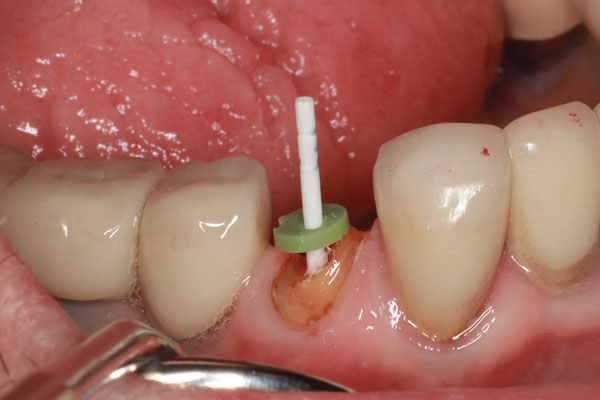

Un paciente se presentó con un diente roto (es decir, el diente No. 28) que requirió tratamiento de conducto. Hubo una pérdida significativa de estructura dental; por lo tanto, se consideró necesario un tratamiento posterior y central para sostener una corona (Figura 1). El paciente fue anestesiado y se excavó cualquier caries restante. Después de obtener, evaluar y medir una radiografía, se utilizó un taladro para eliminar aproximadamente dos tercios de la longitud del material de obturación del conducto radicular (Figura 2). Se tomó otra radiografía para confirmar que la profundidad alcanzada era correcta. A continuación, se probó primero el sistema de poste ajustable único (Splendor SAP, Angelus) sin el manguito para determinar si estaba completamente asentado (Figura 3). Luego se probó con el manguito y se consideró que encajaba bien (Figura 4).

Imagen 2 Se utilizó un taladro para retirar el material de relleno endodóntico a la profundidad ideal.

Imagen 3 Prueba de la publicación Splendor SAP para garantizar asientos completos.